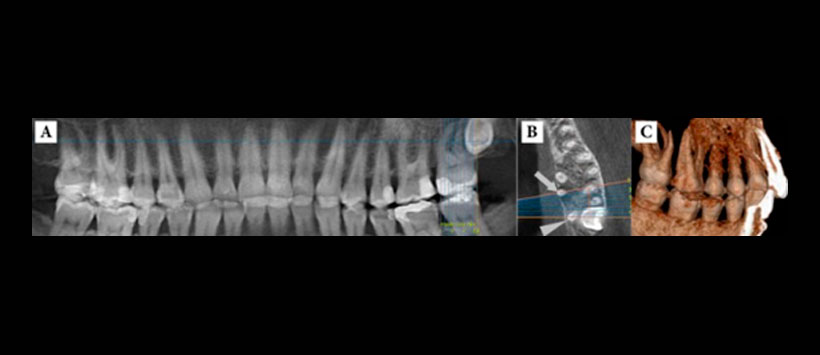

- Diagnosticos diferenciales de tipos de raices – Figura 4